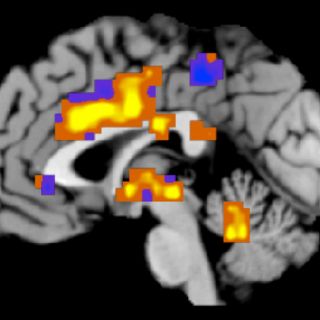

CIUDAD DE MÉXICO (23/MAY/2013).- Impulsos eléctricos sobre el cuero cabelludo de los pacientes con epilepsia parece ser una opción efectiva en la reducción de crisis y sin efectos secundarios adversos, según resultados preliminares de laboratorio, afirmó la investigadora Luisa Lilia Rocha Arrieta.

Explicó que han encontrado que ese tipo de estimulación en animales reduce la excitabilidad del cerebro, por lo que intentan encontrar un tipo de estimulación que sea accesible a cualquier tipo de persona que no requiera la introducción a nivel intracerebral de electrodos o la estimulación del nervio vago que implica una cirugía.

Explicó que aún es necesario hacer diversas pruebas para asegurar que no haya efectos secundarios adversos peores que la misma crisis, ya que si este tipo de estimulación causara demasiada supresión de la actividad cerebral, podría derivar en padecimientos como la depresión.